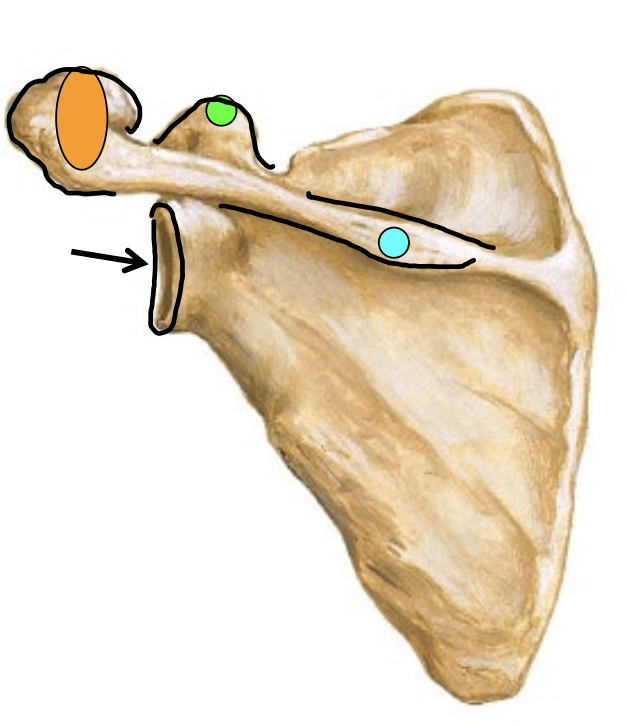

What is the arrow locating in this image?

Glenoid Fossa

What is the blue dot locating in this image?

Spine of scapula

What is the orange dot locating in this image?

Acromion process

What is the green dot locating in this image?

Caracoid process